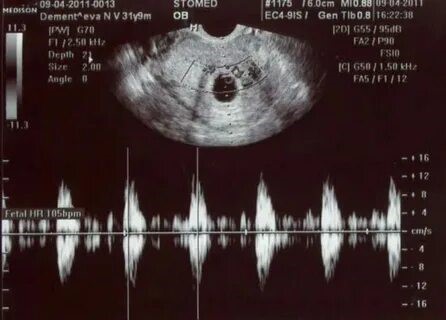

УЗИ ПЕРЕД АБОРТОМ

Рекомендовано  УЗИ матки и придатков  (до 9.6 недель беременности) или УЗИ плода (после 10° недель беременности) перед медицинским абортом с целью диагностики беременности, ее локализации, определения соответствия плодного яйца/эмбриона/плода сроку беременности, наличия сердцебиения эмбриона/плода с демонстрацией   его изображения и сердцебиения (при наличии), наличия и состояния (при его наличии) рубца на матке, расположения хориона/плаценты  (предлежания  плаценты, прикрепления в области рубца при его